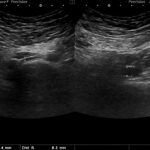

Fig. 2: a) Examen ecográfico por vía transvaginal, que muestra vena ovárica izquierda ectásica de 7.5 mm. b) Examen ecográfico por vía transvaginal, demostrando vena ovárica derecha normal, de 2.5 mm.

Hallazgos imagenológicos. En el eco Doppler ginecológico por vía transvaginal se observa varicocele pelviano (Fig. 1). La vena ovárica derecha mide 3.8 mm, y la izquierda, ectásica, 7.4 mm (Fig. 2). En el eco Doppler abdominal se visualiza la vena renal izquierda, de 3.1 mm en topografía del compás aorto-mesentérico y 8.1 mm en el segmento proximal al riñón izquierdo, con una velocidad 50cm/s en el compas y 30cm/s en el segmento proximal al riñón. El estudio corresponde en primera instancia a un síndrome de Nutcracker (Fig. 3).